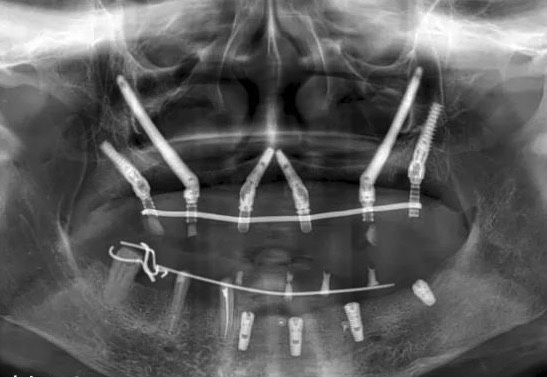

穿顴種植牙是上頜骨嚴(yán)重骨吸收情況下的一種有效替代治療方法,也可被用于上頜骨缺損的修復(fù)治療,既避免了大量的植骨手術(shù),且能明顯縮短種植治療周期。

效果展示

手術(shù)方式

1. 骨量充足的 1 區(qū)及雙側(cè)缺骨的 2、3 區(qū):建議 2-4 顆傳統(tǒng)軸向種植體位于 1 區(qū),雙側(cè) 2 或 3 區(qū)各加一顆顴骨種植體。

2. 骨量充足的 1 區(qū)及一側(cè)缺骨的 2、3 區(qū):建議缺骨側(cè) 2、3 區(qū)一顆顴骨種植體,對側(cè) 2、3 區(qū)及 1 區(qū)采用常規(guī)種植體。

3. 缺骨的 1 區(qū)及骨量充足的 2、3 區(qū):一顆顴骨前種植體加后方常規(guī)種植體即可。

4. 1、2、3 區(qū)均缺骨:4 顆顴骨種植體即可。

避免取骨、植骨等附加手術(shù),而且種植當(dāng)天可以短時(shí)間戴固定牙,能實(shí)現(xiàn)即刻負(fù)重,大大縮短了治療時(shí)間。是上頜骨重度骨吸收情況下的一種有效替代治療方法,也可被用于上頜骨缺損的修復(fù)治療,既避免了大量的植骨手術(shù),且能明顯縮短種植治療周期。